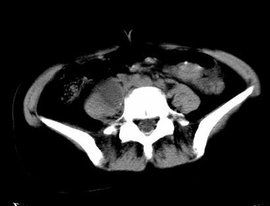

在脊柱的冷膿腫中,除了稀薄的膿汁外,還有大量的乾酪樣物質、肉芽組織、死骨和壞死椎間盤組織。 當冷膿腫的膿汁量過多,膿腫過大時,膿液可沿軟組織間隙蔓延到遠離病灶的地方,到達身體的其它部位。如頸椎結核可形成咽後壁膿腫,過大時可造成呼吸和吞咽困難。但是不同部位的膿腫遵循不同的流向。腰椎結核的膿腫常位於腰大肌內,稱為腰大肌膿腫。它可以沿肌間隙流到大腿內側,有時甚至會流至膝關節上方。也可流到腰部、骶前,破潰後形成經久不愈的竇道,流膿不止。少數腰大肌膿腫可穿入闌尾、膽囊、結腸、腹腔,膿腫浸入的範圍可以很廣。而胸椎結核膿腫少量時為梭形,可向上,下蔓延,也可向背部突出,或形成膿胸,肺膿腫,支氣管瘺,甚至穿入食道、胸主動脈等。

因此,熟悉膿腫的流向,將有助於骨結核的診斷和定位。